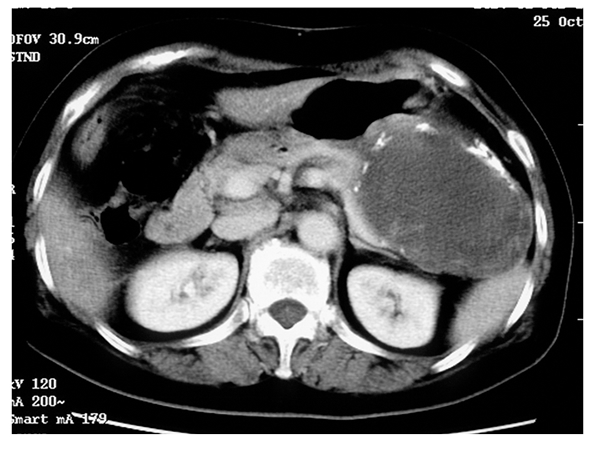

Tipik olarak genç yaşta ve kadınlarda görülür. Kadın-erkek oranı 9/1’dir. Bilimsel sınıflamada kist grubu altında yer alsa da hem radyolojik görüntüsü hem de kesit görüntüsü sıvı içerikten farklıdır. Düşük grade’li kanser olarak değerlendirilen bu tümör iyi seyirli kötü huylu tümör olarak da değerlendirilebilir. Hastaların çok büyük çoğunluğunda cerrahi olarak çıkartıldığında tam tedavi (KÜR) sağlanmış olur. Hastaların az bir kısmında uzak organlara yayılım (metastaz) görülebilir.

Seröz Kistik Neoplazi

Seröz kistler birden fazla görünümle karşımıza çıkabilirler. Mikrokistik olanları radyolojide balpeteğini andırır görüntüdedirler. Oligokistik formu tek büyük kist görüntüsündedir ve bu nedenle diğer kist tipleriyle karıştırılabilirler. Seröz kistler kanserleşmezler. Bu nedenle şikayete neden olmuyorlarsa ve tanıları konusunda bir şüphe yoksa cerrahi tedavi gerektirmezler.